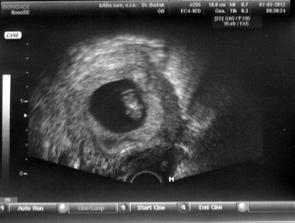

1.3. opět návštěva dr. kvůli špinění, vše v pořádku - miminko 9+2tt - vystavena těhotenská průkazka